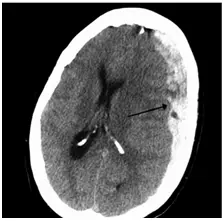

- 檢查方式:這是一張腦部**未打顯影劑的電腦斷層(Non-contrast CT)**橫切面影像。

- 病灶位置與形狀:

- 在影像右側(病人的左側大腦半球,CT影像左右相反)可以看到一片高密度(白色)的出血區。

- 該出血區呈現典型的**新月形(Crescent shape)**或凹透鏡狀,沿著大腦半球的凸面分佈。

- 箭頭所指之處顯示血塊內緣呈現凹陷狀,順著腦組織表面延伸,這是硬腦膜下出血的特徵。

- 佔位效應(Mass Effect):

- 出血造成明顯的佔位效應,壓迫左側大腦半球。

- 可見**中線偏移(Midline shift)**向右側(病人的右側)。

- 左側側腦室受壓變形甚至消失。

- 綜合判斷:高密度的新月形出血,且造成腦實質壓迫,為典型的**急性硬腦膜下出血(Acute Sub